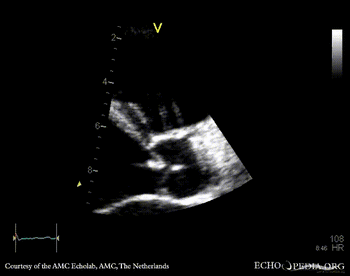

E00808.jpg

Pulsed-wave Doppler signal of flow in abdominal aorta: holodiastolic flow reversal